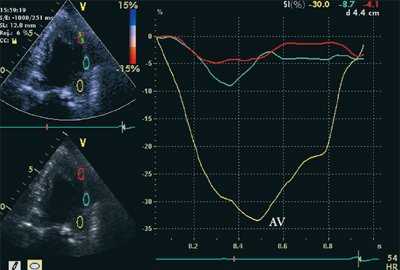

- Пиковая скорость и амплитуда систолической деформации: SR (strain rate) и ST (strain).

Оценивались также показатели тканевой допплерографии, характеризующие феномен ПСУ.

- Постсистолическая деформация (STps).

На рис. 3-5 приведены различные варианты ПСУ у больных с постинфарктным кардиосклерозом.

![Кривые деформации миокарда в норме]()

![Кривые деформации миокарда при постинфарктном кардиосклерозе]()

б) При постинфарктном кардиосклерозе. У больного регистрируется высокоамплитудный пик постсистолической деформации (STps).

Вертикальная линия (AV) на рис. 3-5 соответствует времени закрытия аортального клапана. На представленных графиках также отмечается наличие базально-верхушечного градиента (снижение пиковых миокардиальных скоростей, продольного систолического смещения и деформации от основания к верхушке левого желудочка).